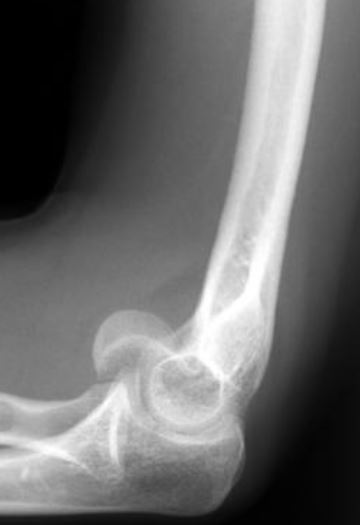

A 24-year-old male sustains the isolated, closed injury seen in Figure A as the result of a fall. What surgical treatment is recommended for this fracture?

The radiograph shows a comminuted olecranon fracture with extension distally past the coronoid. Plate fixation is recommended for olecranon fractures with significant comminution and those that extend distal to the midpoint of the trochlear notch, which is present in this instance. Hak et al.